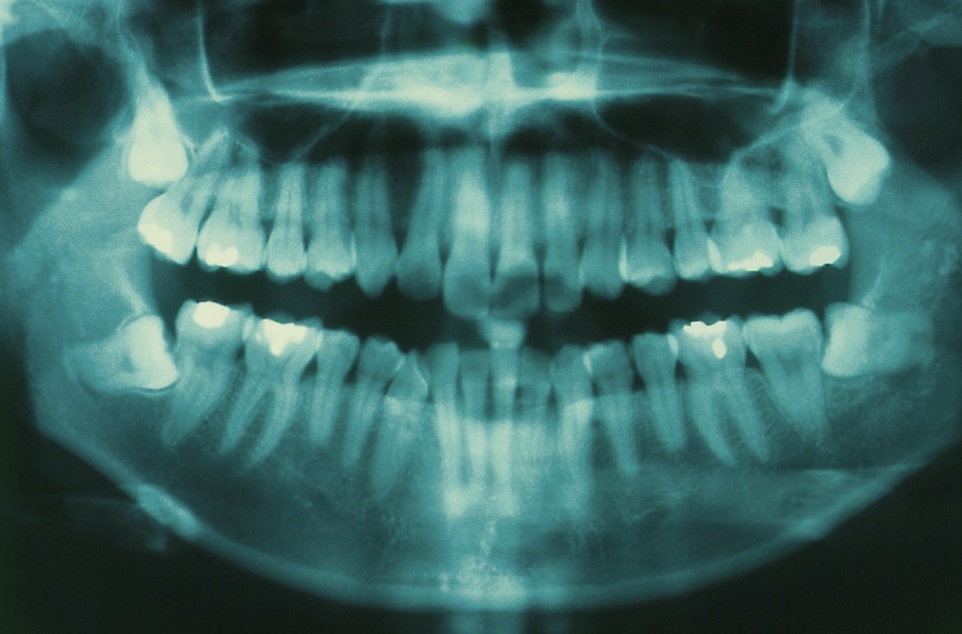

Panoramic Dental X-ray Of Impacted Wisdom Teeth - Stock Image - M782

www.sciencephoto.comwisdom teeth impacted ray panoramic dental

www.sciencephoto.comwisdom teeth impacted ray panoramic dental

Impacted Wisdom Teeth, X-ray - Stock Image - M782/0249 - Science Photo

www.sciencephoto.comwisdom teeth impacted ray stock

www.sciencephoto.comwisdom teeth impacted ray stock